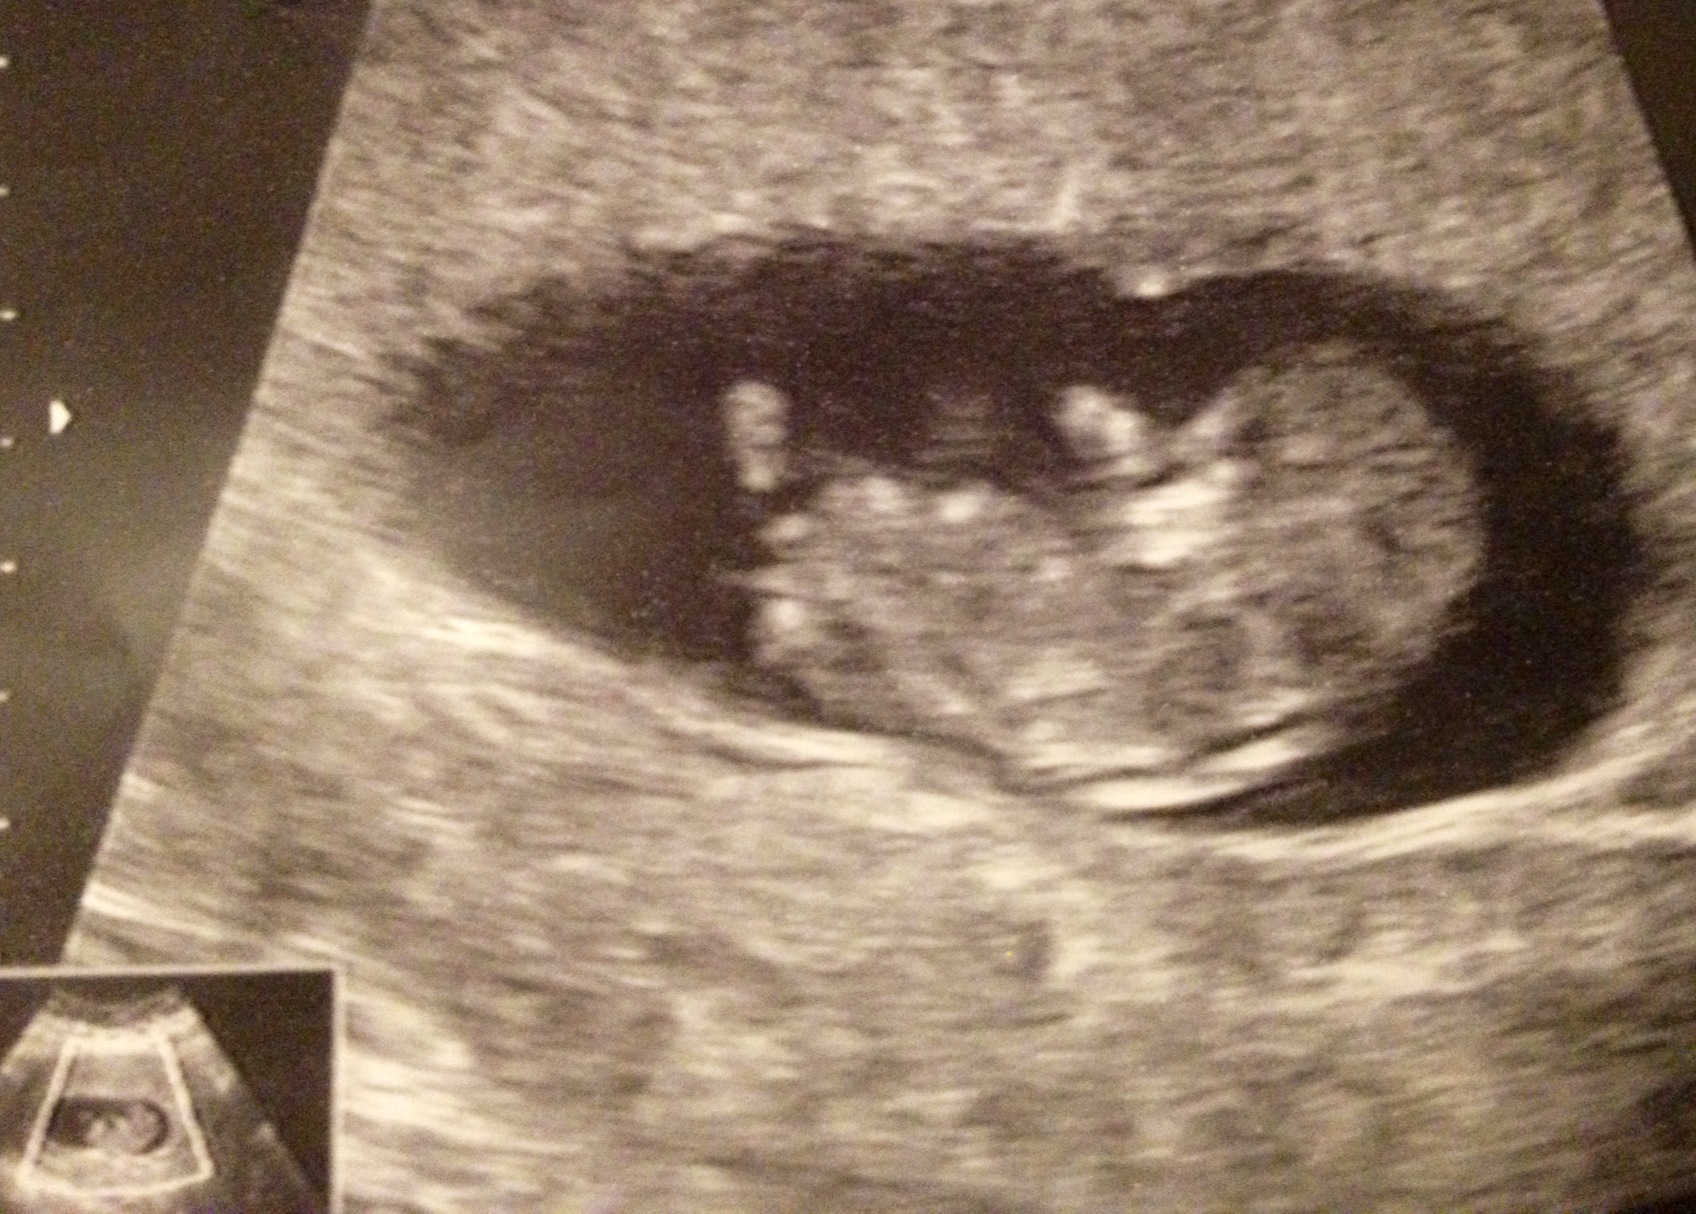

I had a scan today because I've had some bleeding. After learning that everything is ok, I was telling the sonographer that I have three boys. So she looked (toilet shot) and said, "My guess is that this is boy #4! There's definitely something between the legs." My heart sank for just a minute, but I'm honestly relieved that all is well with the pregnancy. Plus I have no regrets about my sway...so if it is a boy, I know I did all I could.

I was surprised that she made a prediction at all this early especially based on that angle...not nub. (I didn't ask her about the nub)

I don't know much about nub shots and if they can be seen in these pics or not. Or if they'd even be accurate this early.

Attachment 23424